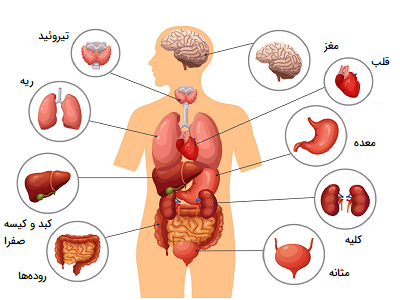

عکس داخل شکم انسان. در این همان طور که مشخص است شکم حالت بیضی شکل پیداکرده و این بیضی که کناره های شکم کشیده شده است. تعداد سلول های بدن انسان حدود ۳۷ ۲ تریلیون تخمین زده شده اند. Abdomen که در زبان عامه به غلط به آن دل نیز می گویند در آناتومی به قسمتی از تنه گفته می شود که مابین دیافراگم از بالا و سطح فوقانی لگن خاصره از پایین قرار دارد. ربات دیدنی ربات انساننمای چینی به صورت یک دختر جوان ساخته شده و جیا جیا نامگذاری شده است این ربات طوری برنامهریزی شده که میتواند صحبت کند و احساسات خود را از طریق تغییرات در چهره حالات.

شکل دوم شکم مادری را نشان می دهد که جنین دختر دارد. وحشت مادر از عکس سونوگرافی جنین داخل شکمش عکس. تصاویر جالب از داخل مغز و نخاع انسان آخرین نیوز. بدن انسان کل ساختار انسان است که سر گردن تنه سینه و شکم دو بازو و دست ها و دو ساق پا و پاها را شامل می شود.